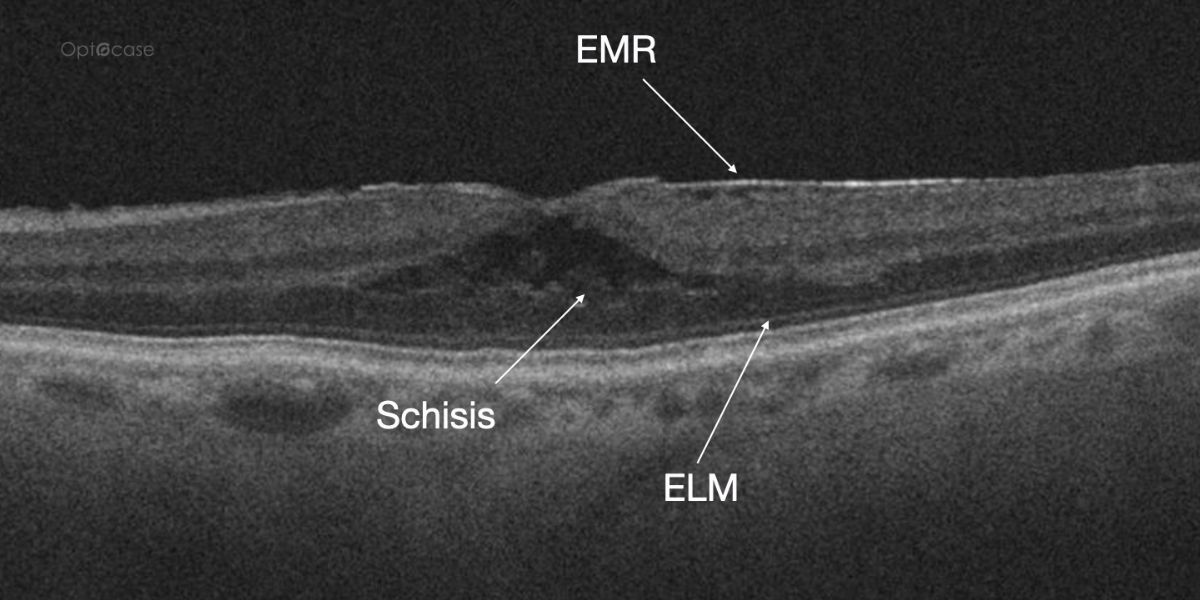

A 73-year-old presents with new distortion. Why?

Here there is loss of the regular macular depression. There is a bright line present on the surface of the retina. In addition, there is separation of the retinal layers in the inner retina.

The patient was diagnosed with a schisis secondary to an epiretinal membrane. This complication is seen in over 50% of ERMs (video).